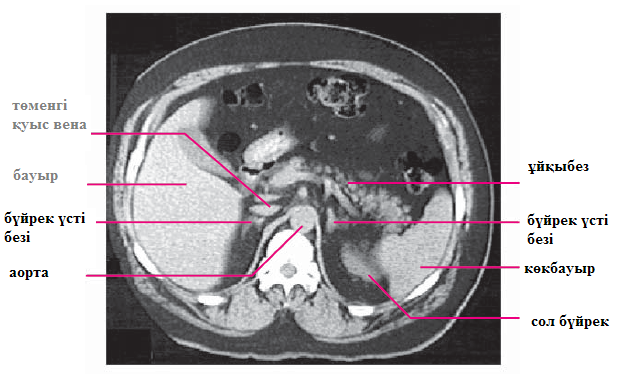

Бүйрек үсті безін визуализациялау үшін КТ және МРТ қолданылады. Бүйрек үсті безі ауруларын диагностикалауда аталған екі аспаптық зерттеу әдісінің ақпараттылығы бірдей. КТ-нің артықшылығы- бағасының арзандылығында. Бүйрек үсті безінің жоғары полюсі томографиялық кесіндіде XI-XII кеуде омыртқасына сәйкес келеді, жиі төменгі қуыс көктамырының артында үлкен емес жолақ ретінде көрінеді. Оның сол жағында диафрагманыңы оң жақ аяқшасы мен қолқаның құрсақтық бөлімінің диафрагмаішілік бөлігі жатыр. Оң жағында бауырдың оң жақ бөлігі орналасқан. Сол жақ бүйрек үсті безі «Y» әріпі немесе үшбұрыш пішіні түрінде көрініп, сол жақ бүйректің жоғарғы полюсінен медиальды, алға қарай орналасады. Сол жақ бүйрек үсті безінің алдында, ұйқыбезі құйрығының артында көкбауыр артериясы жатыр. КТ мен МРТ кезінде бүйрек үсті безінің қыртысты және милы заты ажыратылмайды. Екі әдіс те бүйрек үсті безінің көлемін, онда дамыған патологиялық түзілістерді анықтауға, олардың көлемі мен пішінін бағалауға мүмкіндік береді (4.6 және 4.7сурет).

4.6 сурет. Қалыпты жағдайдағы бүйрек үсті безінің компьютерлі томограммасы